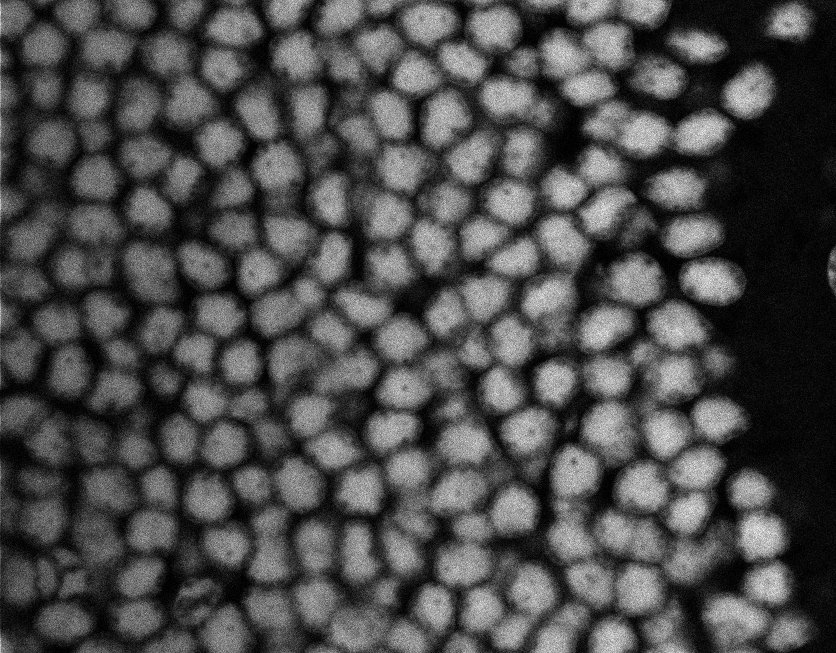

Actin

Nuclei